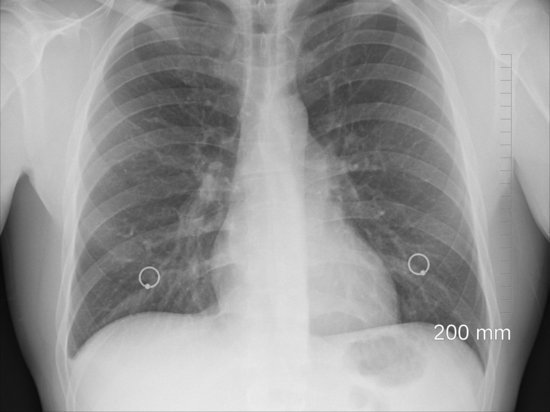

"Сегодня он покинул больницу. 70% легких – белое пятно, то есть 30% сохранилось", - рассказал Развожаев.